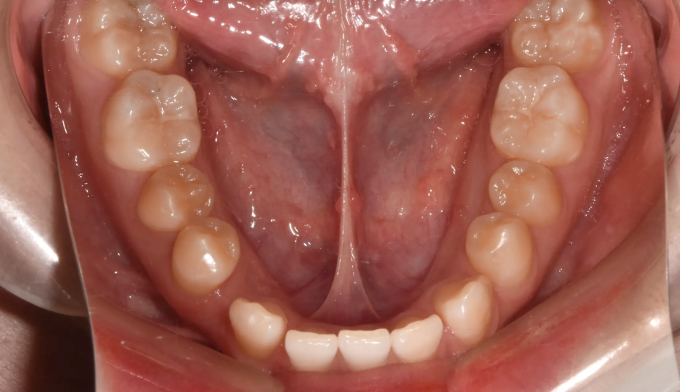

아래 앞니 하나가 선천적으로 부족한 경우이지만 주걱턱 경향으로 인해 아랫니가 윗니를 계속 자극하여 윗니까지 벌어진 케이스입니다. 윗니의 공간을 닫아주기 위하여 아래앞니를 먼저 후방이동시켜줬고, 이후에 벌어진 윗 앞니를 가지런하게 모아 마무리하였습니다. 아래앞니 하나가 부족하기때문에 위아래 가운데선을 맞추지 않고 종료하였습니다. 총 교정기간은 11개월입니다.